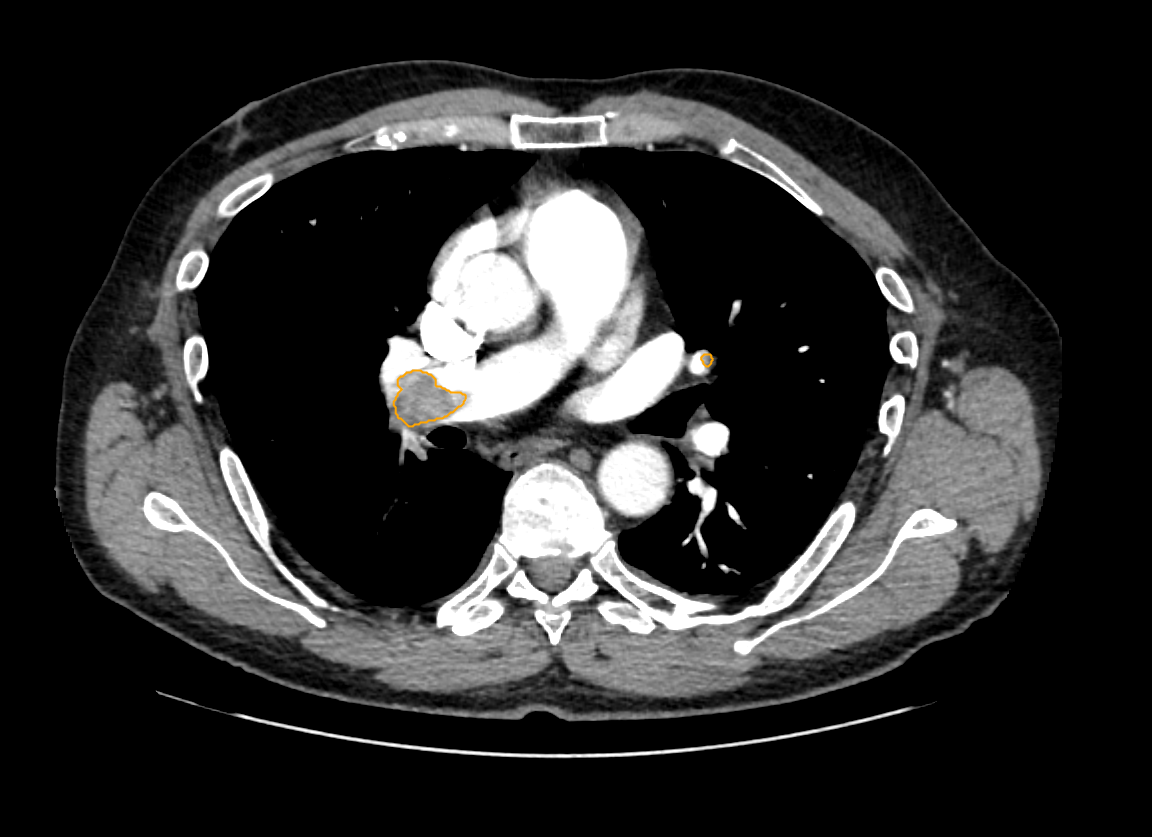

CT Eye helps radiologists to identify pulmonary embolism (including incidental PE in contrast studies), lung nodules, and lung consolidation.

CT Eye™ is designed to assist radiologists reviewing adult chest CT studies by identifying radiological signs associated with pulmonary embolism (including incidental PE in contrast studies), lung nodules, and lung consolidation. The system helps prioritise studies where these findings may be present, provides study-level localisation of suspicious areas, and performs automated quality checks by comparing image content with the radiologist’s final report using integrated NLP analysis.